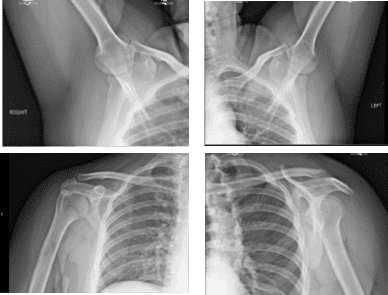

For previous surgery, none. The patient presented X Ray results that showed unremarkable radiographs of the bilateral shoulder.

X-ray Bilateral Shoulders